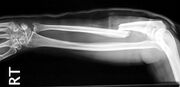

| 14:32, 13. Jan. 2011 | Gebrochene Speiche.jpg (Datei) |  |

51 KB | Gudrun | '''Gebrochener Arm - Speiche'''<br> Bildquelle: commons.wikimedia.org <br> Autor: Jane Agnes | 1 |